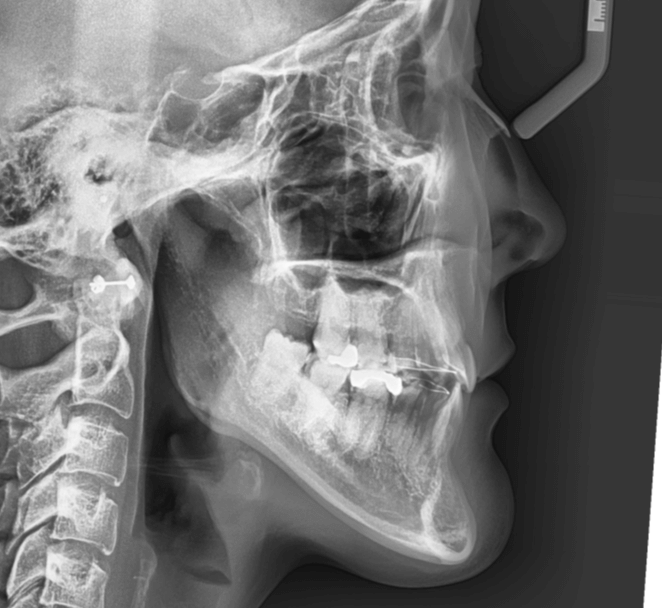

咬み合わせが逆であること(反対咬合)が気になる

| 年齢・性別 | 15歳 女性 |

|---|---|

| 主訴 | 咬み合わせが逆であること(反対咬合)を気にされて来院された女性。見た目や機能面の改善を希望されていました。 |

| 治療期間・回数 | 4年4ヶ月・28回 |

| 費用 | 900,000円 |